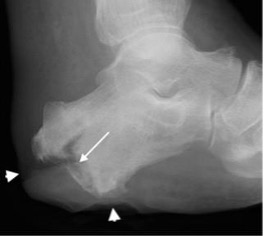

Kohler’s disease with flattening and sclerosis of the navicular (arrow)

Mueller-Weiss syndrome with collapse of the lateral navicular and medial navicular subluxation